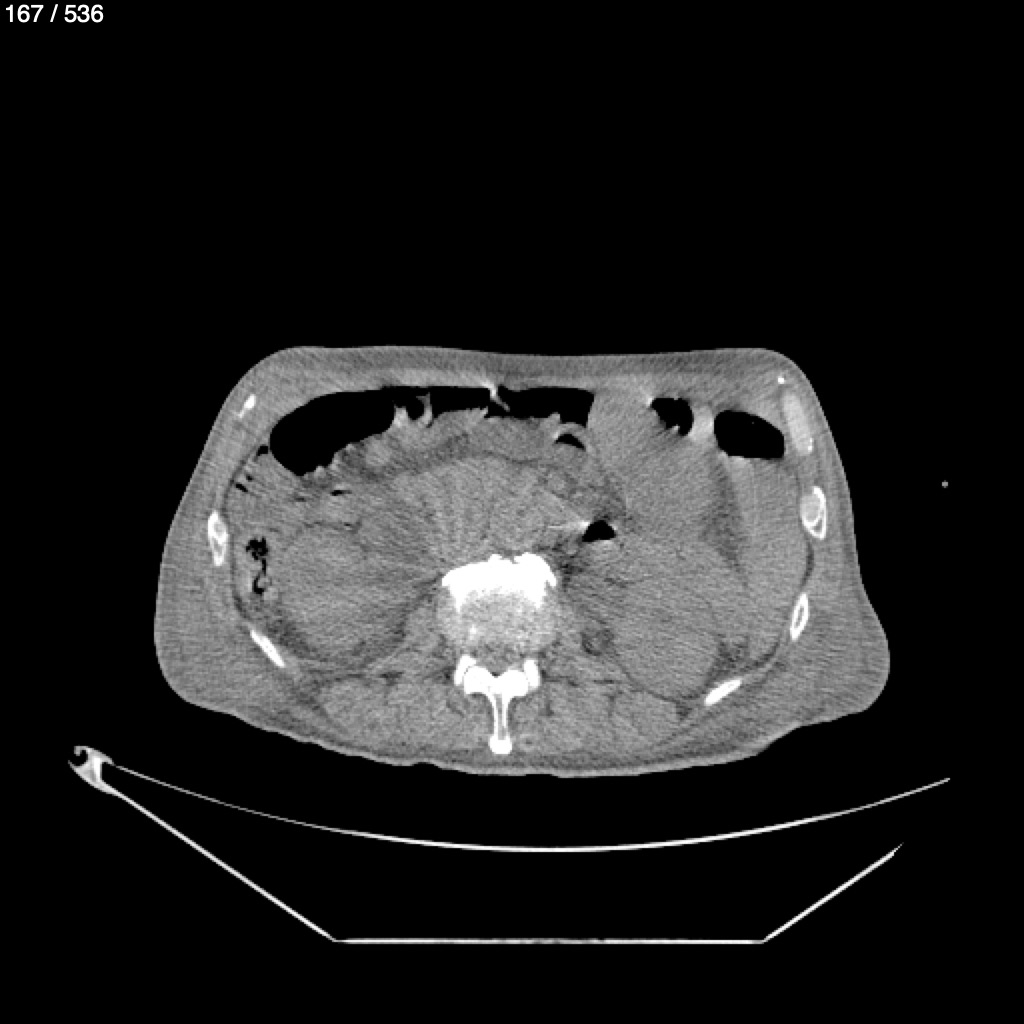

Angel Villalobos Palomeque 73 A - T.C Abdomen Simple